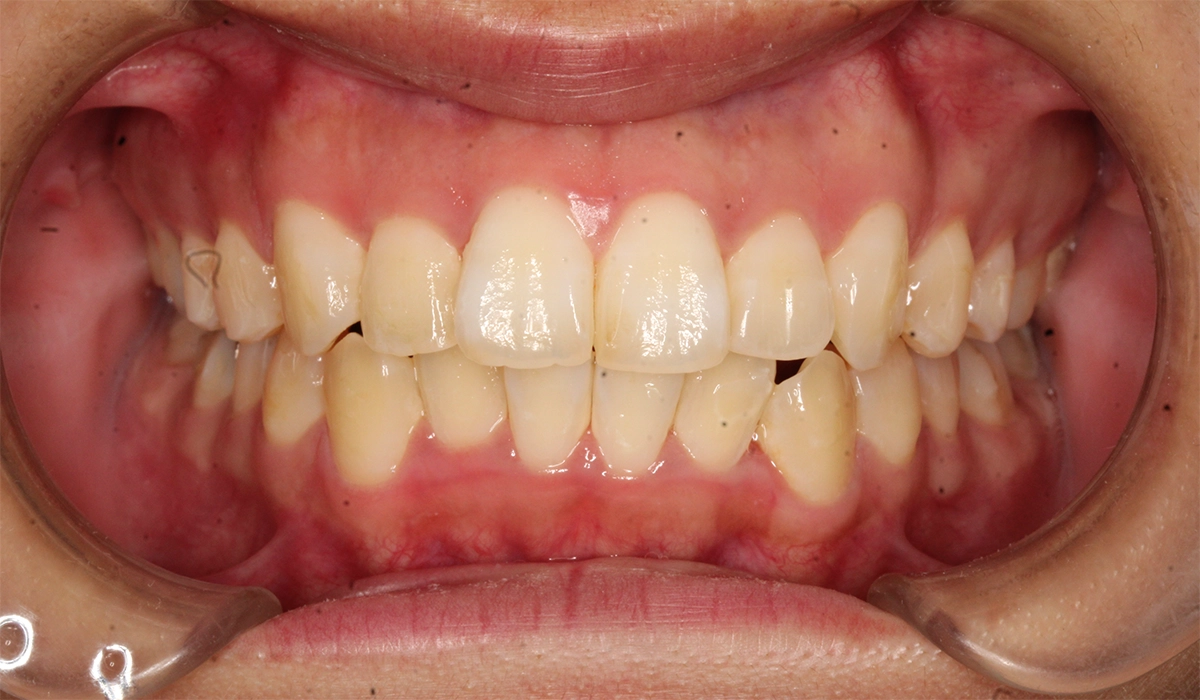

術前:正面

術後:正面